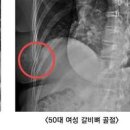

갈비뼈 골절 증상 회복기간 갈비뼈 금갔을때 통증 2025.07.18해당카페글 미리보기

갈비뼈 골절 회복기간 그리고 갈비뼈 금갔을때 통증 관리 방법 갈비뼈는 우리 몸의 중요한 장기인 심장과 폐를 보호하는 역할을 합니다. 하지만 외부의 강한 충격이나 반복적인 스트레스로 인해 골절되거나 금이 가는 경우가 발생할 수 있습니다. 갈비뼈...